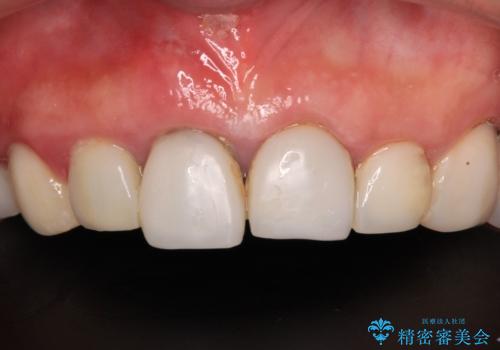

[ 歯周病・矯正・セラミック補綴 ] 歯の総合的なマネージメントを行う包括的歯科治療の実践

![[ 歯周病・矯正・セラミック補綴 ] 歯の総合的なマネージメントを行う包括的歯科治療の実践の症例 治療前](https://seimitsushinbi.jp/wp/wp-content/uploads/2025/10/7db12d5413070a950bc6275b957b7f9f-500x350.jpg?v=1760767674)

![[ 歯周病・矯正・セラミック補綴 ] 歯の総合的なマネージメントを行う包括的歯科治療の実践の症例 治療後](https://seimitsushinbi.jp/wp/wp-content/uploads/2025/10/eaeb8f32e6e2496b4cca2d55d85ba36c-500x350.jpg?v=1760768149)